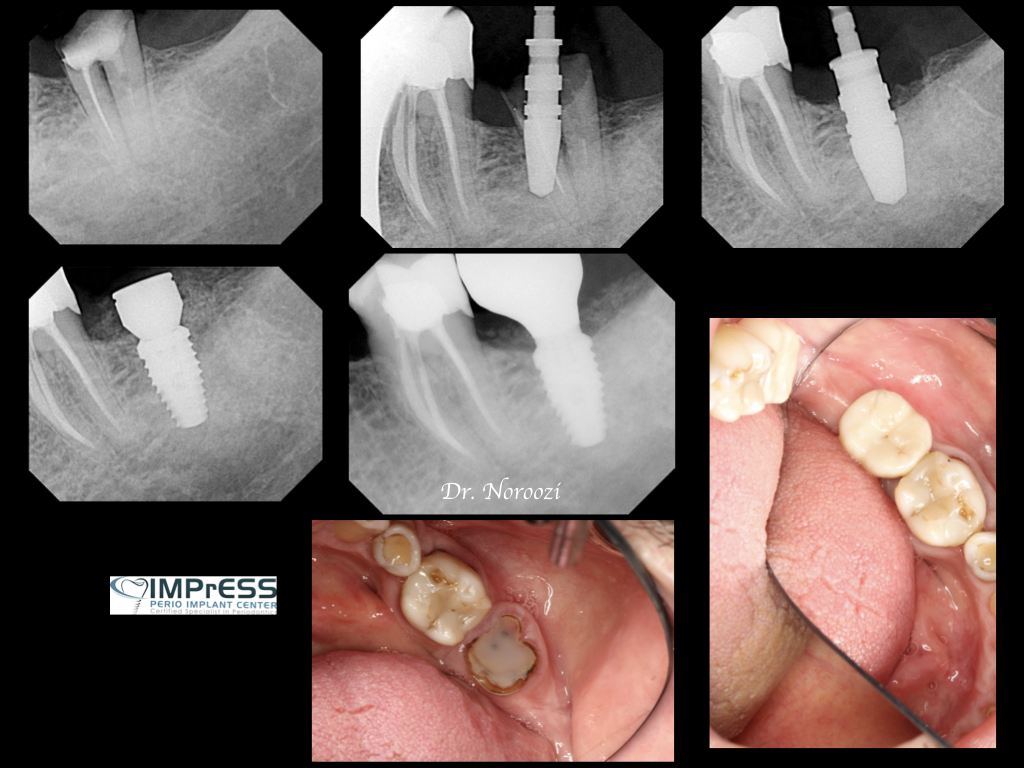

Immediate Implant Placement in Molar Extraction Site

IMPrESS Perio Implant Center Dr. Noroozi Vancouver Periodontist Implant Specialist Burnaby BC

immediate implant placement in molar site Dr. Noroozi